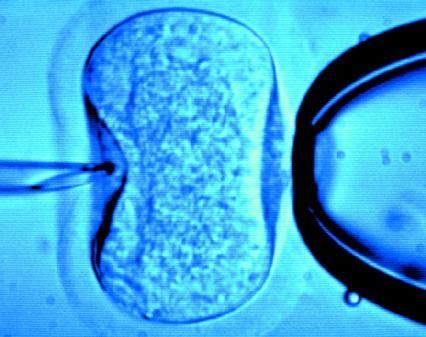

據英國《每日郵報》1月18日報道,英國一位60歲老婦將成為英國接受試管受精最年長者。這位老婦名叫蘇珊·托勒夫森,是一位退休教師,到今年10月她就滿60歲了。2008年,蘇珊曾去俄羅斯接受試管受精,在英國生下了她的第一個孩子。

倫敦哈利街的私人診所是英國試管嬰兒手術成功率較高的醫(yī)院之一,醫(yī)生們在上周一同意幫助蘇珊·托勒夫森進行第二次人工受孕。通常情況下,私人診所只在特殊情況下給50歲以上的婦女進行試管受精,例如,患者仍然有月經周期。這件事引起了絕經后婦女是否有生育權利的倫理大討論,現(xiàn)在要求提高生育治療年齡上限的呼聲越來越高。

現(xiàn)在,蘇珊·托勒夫森一家人很幸福,丈夫尼克·邁耶是一位公司經理,比她小11歲,他們的女兒今年2歲。專家表示,蘇珊很健康,她的女兒如果能有一個兄弟姐妹會更好,于是蘇珊想再次接受試管受精!缎瞧谌锗]報》獲悉,倫敦哈利街私人婦女診所的高級工作人員已經同意為蘇珊做試管受精,還決定幫助另一位57歲的老婦受孕。(海瀾)